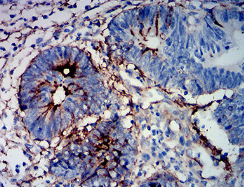

MUC16 Mouse Monoclonal antibody[4C8C8]

IHC    1/200-1/1000